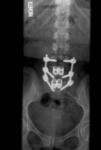

2010-01-26-03.jpg Date: 02/09/10 taken after the posterior portion of the surgery on 1/26/10 - these are the titanium rods and screws, as well as the titanium cages

2010-01-26-04.jpg Date: 02/09/10 my favorite of the images, taken after the posterior portion of the surgery on 1/26/10, showing the titanium rods and screws, as well as the titanium cages that replaced the discs at L4-L5 and L5-S1. this one clearly and unquestionably demonstrates that i am, in fact, BIONIC ;)